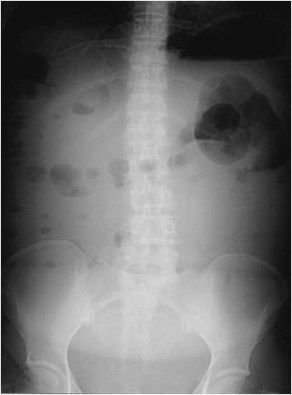

SIGNOS DE ASCITIS EN LA RADIOGRAFÍA DE ABDOMEN

Esta imagen coronal de TC de abdomen nos puede ayudar a entender algunos de los signos de ascitis en la radiografía: el borramiento del ángulo inferior hepático, el ensanchamiento de la banda del flanco o la separación y disposición central de las asas de intestino delgado.

SIGNO DEL ÁNGULO HEPÁTICO

El ángulo infero-lateral del hígado es normalmente visible en la radiografía simple de abdomen gracias a la presencia de grasa properitoneal. El ángulo se borra por la presencia de líquido (ascitis) en esta localización, como vemos en la imagen.

Este signo tiene un valor limitado como indicador de la presencia de líquido intraperitoneal, ya que el ángulo hepático no se ve en más de un tercio de sujetos normales, especialmente en radiografías de escasa calidad técnica. Sin embargo, si la grasa extraperitoneal lateral al hígado se ve con claridad, debe verse también el ángulo hepático; de lo contrario, debe sospecharse la existencia de líquido intraperitoneal.

Signo de ascitis en la radiografía simple de abdomen, justificado por la presencia de abundante líquido sobre el que flotan las asas intestinales. En la imagen se observa un aumento de densidad difuso (en “vidrio deslustrado”), y asas agrupadas en posición centroabdominal.

SIGNO DEL ABDOMEN EN VIDRIO DESLUSTRADO

Signo de ascitis masiva en la radiografía simple de abdomen. El signo consiste en el aumento de la densidad abdominal, la borrosidad de los contornos de los órganos intraabdominales y el borramiento de planos grasos, producidos como consecuencia de la presencia del líquido ascítico. El efecto recuerda a una imagen vista a través de un vidrio esmerilado.